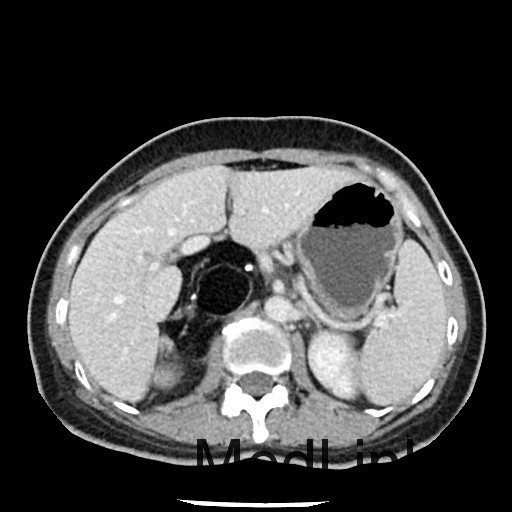

查体:神清,一般情况好,无水牛背、满月脸,皮肤无紫纹。 辅查:全腹CT平扫+增强提示右侧腹膜后区占位性病变,畸胎瘤可能性大。

讨论:本例畸胎瘤因发生在肾上腺区,因此表现为发作性高血压。一般只要在CT图像上看到钙化、脂肪密度等特征性征象,增强扫描实性成分轻度强化,畸胎瘤的诊断一般不难。不过非成熟性的畸胎瘤一般缺少钙化和脂肪成分,此时要与腹膜后其他来源的实性肿瘤相鉴别。本例病理大体能够看到毛发,也是畸胎瘤比较特征性的病理表现。